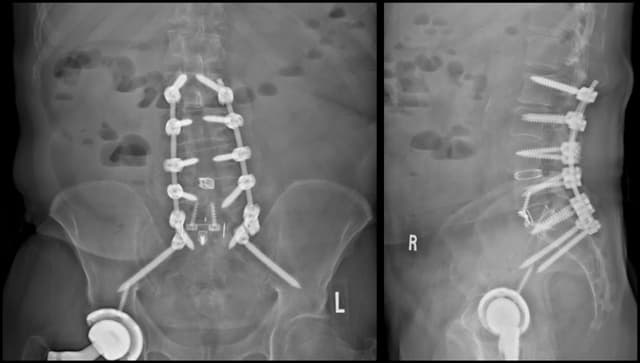

Pre-op

Post-op